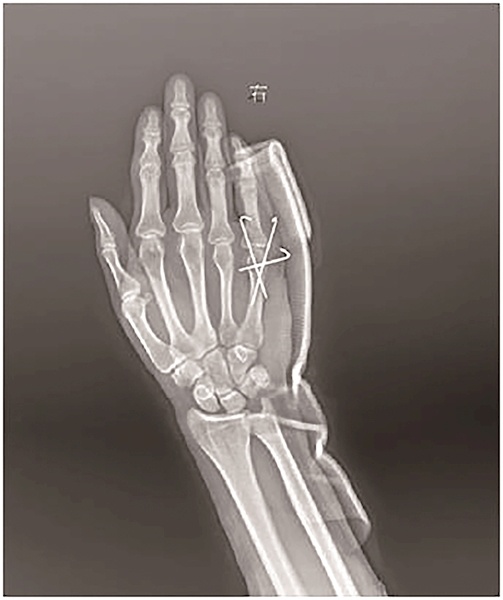

王先生检查诊断为“拳击手骨折” 武汉市第四医院供图

武汉市第四医院手外科医生接诊,拍片提示“右手第5掌骨颈骨折”,骨折畸形明显。于是,医生为其进行了内固定手术。术后,王先生手部情况有所改善,恢复得很好。

“如果骨折不严重,可选择石膏固定的治疗方式。”胡锐介绍,对于骨折成角大于30°、骨折不稳定者或骨折波及关节面的,则需手术治疗。